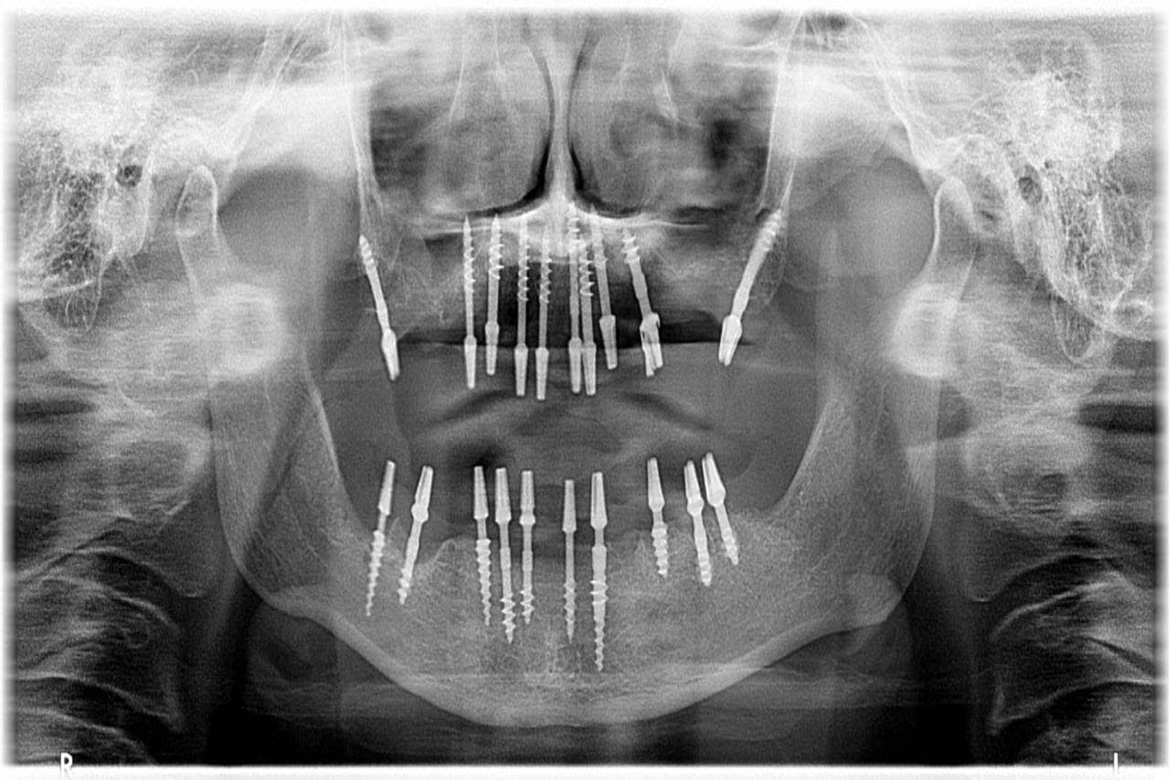

A Dental implant is a titanium post that is placed in your jaw bone which interfaces,integrates or interlocks (as in BASAL IMPLANTS) to provide a strong and secure foundation that replaces your missing teeth permanently.

They preserve the natural bone and also help stimulate fresh bone growth.

They mimic the natural teeth in form and function.